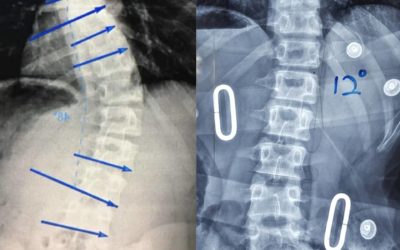

Skoliosis adalah kelainan yang terjadi pada rangka tubuh yang berupa kelengkungan pada tulang belakang. Sebanyak 75-85% kasus skoliosis merupakan idiopatik, yaitu kelainan yang tidak diketahui apa penyebabnya.

Koreksi 75% pada Pasien Skoliosis dengan brace GBW di Malaysia